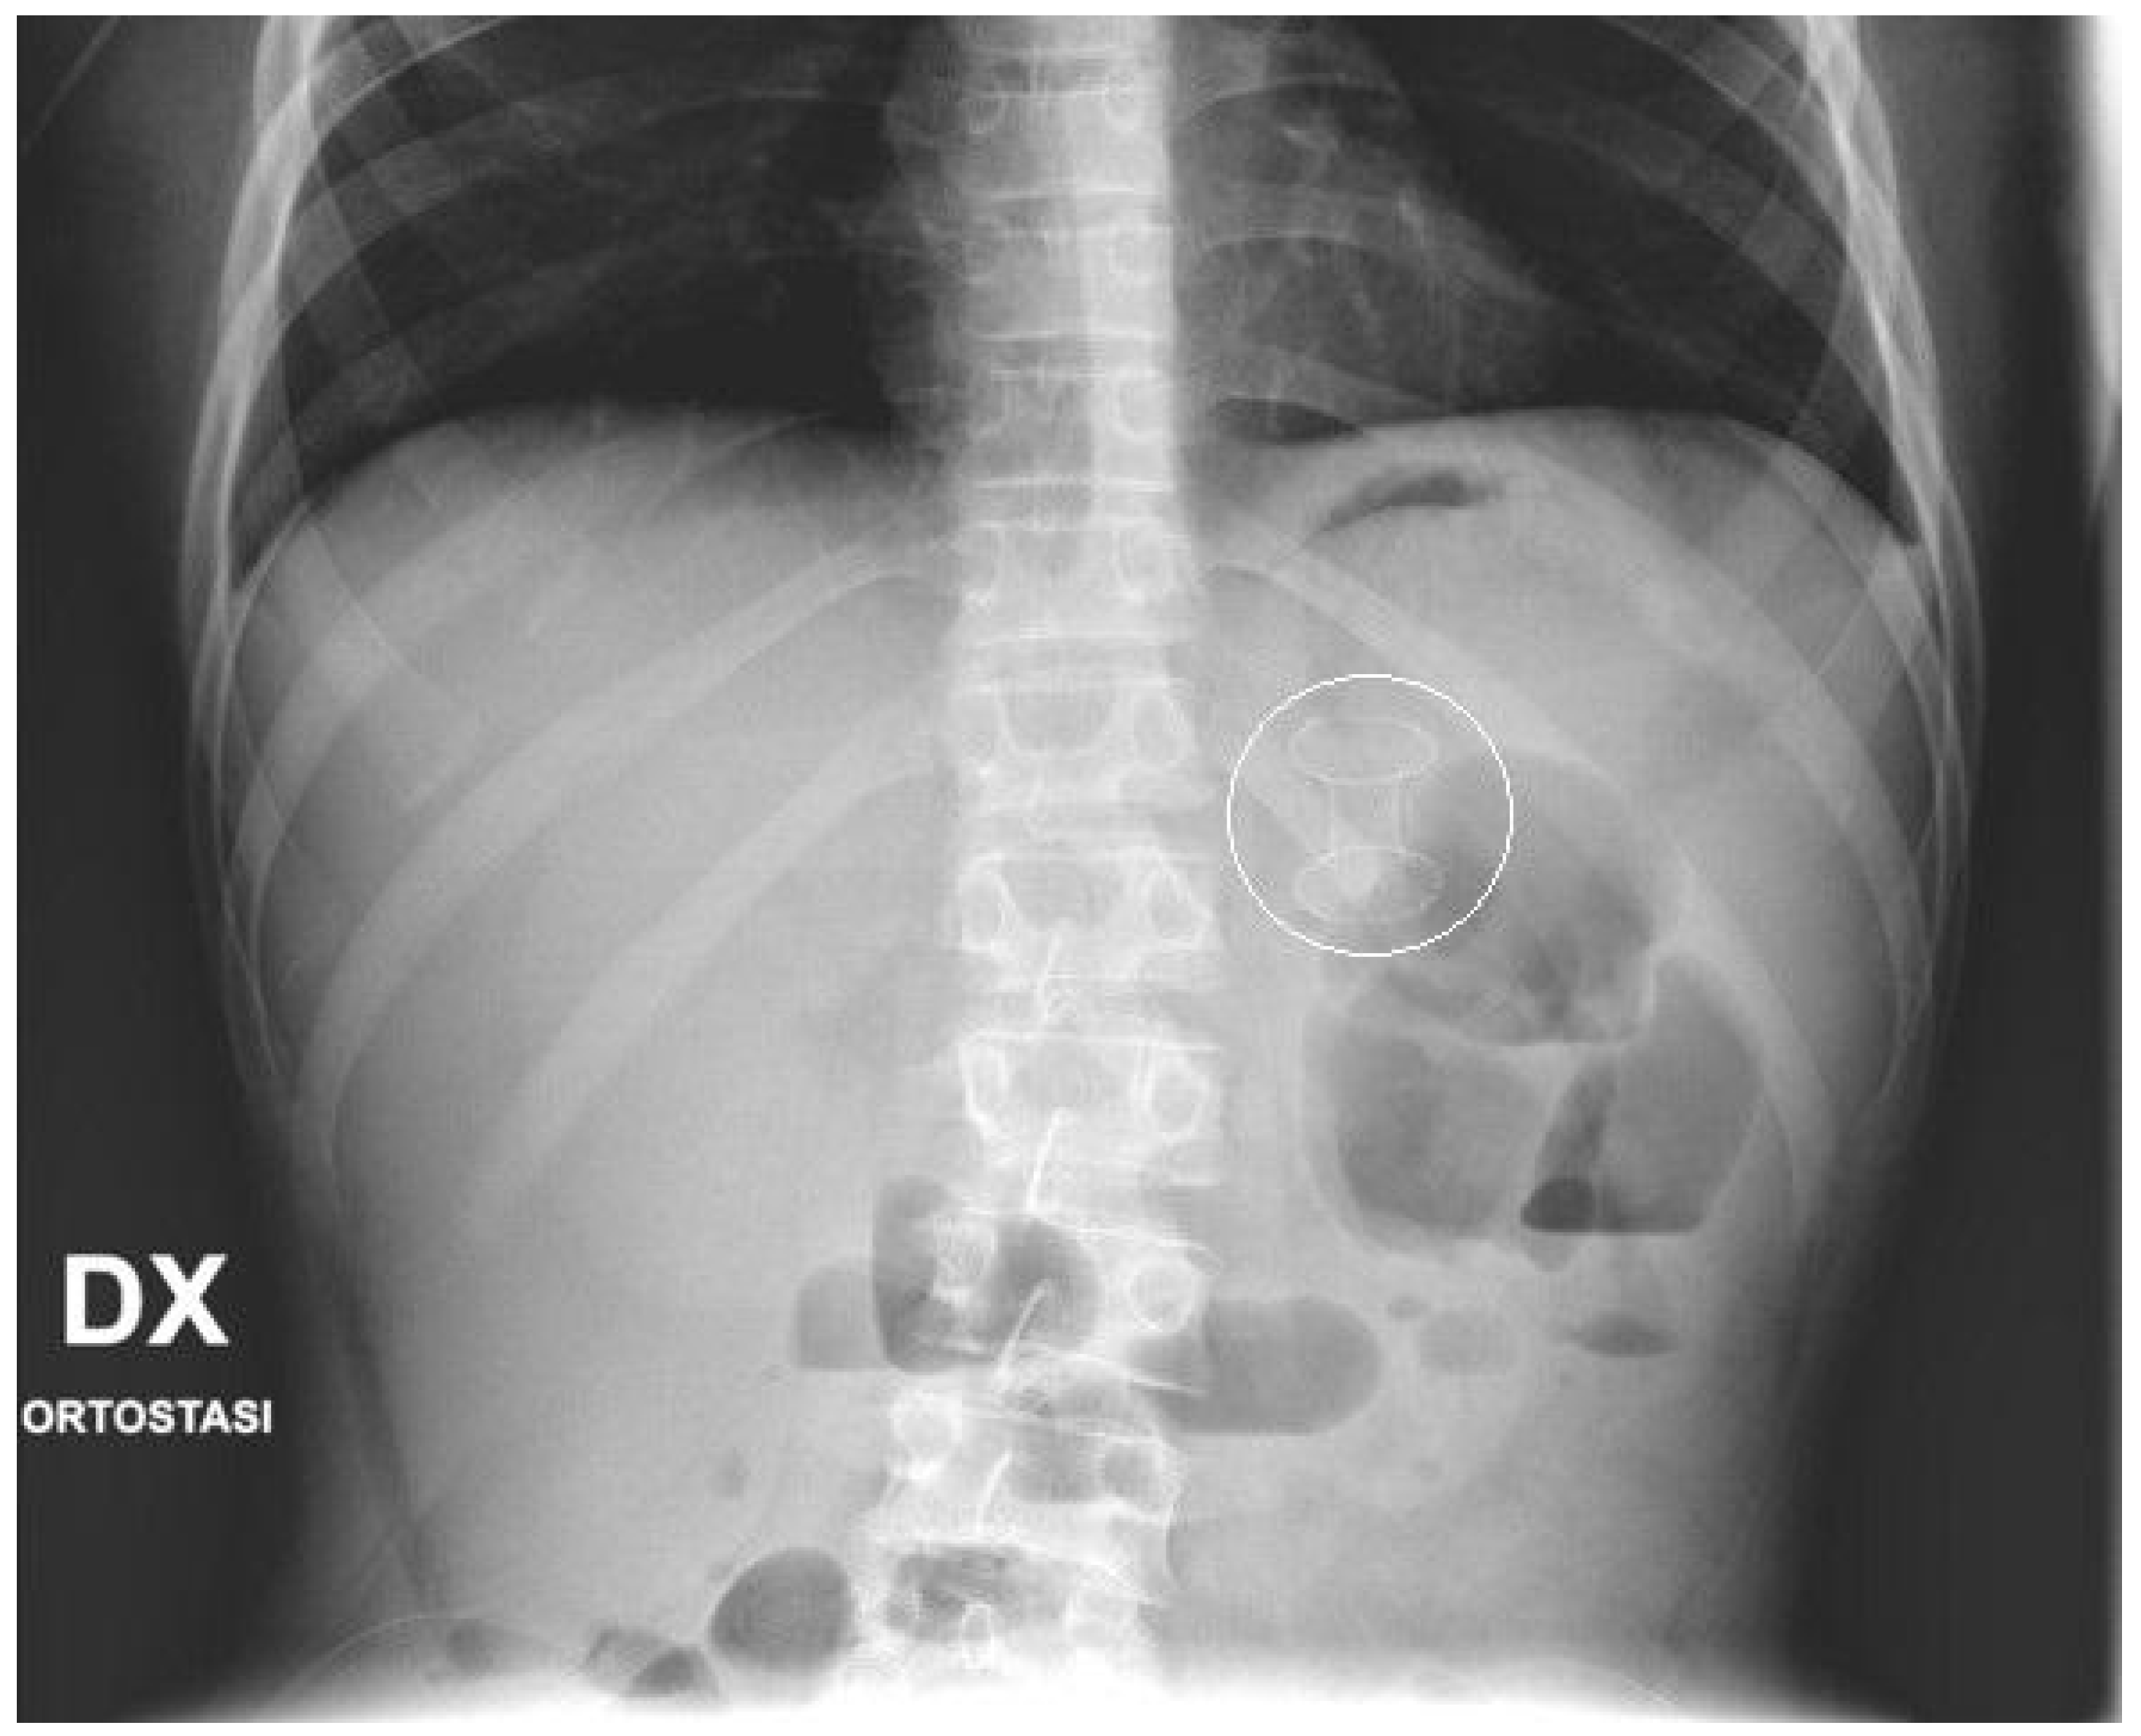

No fluoroscopy was needed during the position of the stent; nevertheless, an X-ray was taken at the end of the procedure (Figure 2). In the following days, the correct position of the stent was confirmed with bed-side US. In the patient with WON, endoscopic necrosectomy sessions was not performed. Post-operative treatment included adequate pain control, supportive care and early enteral nutrition, according to the clinical condition of the patients. Complications occurring after the procedures, such as perforation, bleeding, stent displacement, were carefully documented. The stents were kept in place until resolution of the PFCs, assessed with pre-operative routine echography and/or MRI. When indicated, the stents were electively removed by a simple esophagogastroduodenoscopy, performed as an outpatient procedure.

Figure 2.

Final X-ray. X-ray performed at the end of the procedure that shows the EC-LAMS as a radiopaque dumbbell-shape object projected in the epigastrium.

A 10-year boy affected by T-lymphoblastic lymphoma developed a WON after chemotherapy-induced necrotic-hemorrhagic pancreatitis, with fever, vomit and abdominal pain. Clinical conditions were also complicated by deep vein thrombosis involving the left femoral vein and inferior vena cava. Abdominal CT showed a large WON, with a major diameter more than 22 cm (Figure 5). Considering the worsening of clinical condition and the need to an early resume of the chemotherapy, he underwent a primary EUS-guided cystogastrostomy and EC-LAMS positioning; we did not perform necrosectomy. Post-operative course was uneventful. MRI performed 37 days after the procedure, showed a significant reduction of the WON (Figure 6); subsequent US images were performed for follow-up, until the WON was no more visible. Endoscopic removal of the device was performed 48 days after cystogastrostomy.

Figure 5.

Patient n°3 CT. Necrotic-hemorrhagic pancreatitis (body/tail origin) with voluminous walled-off necrosis developing in the left quadrant (hypochondrium/flank; relations to stomach, spleen, kidney, descending colon), extending craniocaudal about 22 cm.